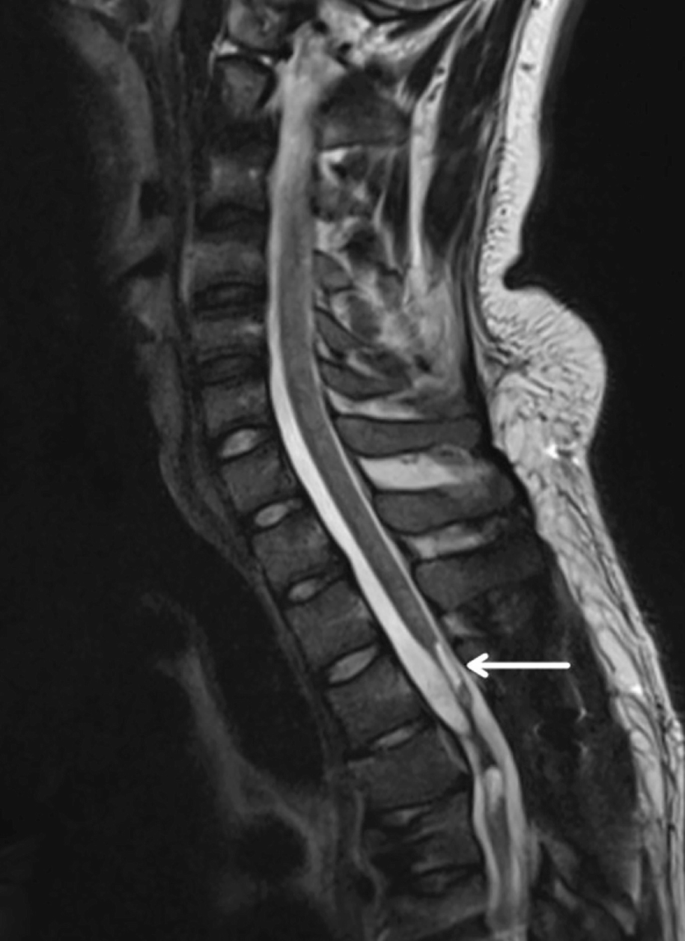

慢性期開始于損傷后約3-6個月,并持續(xù)患者的余生,典型特征是囊腫形成和嚴重的神經膠質瘢痕(圖2)。